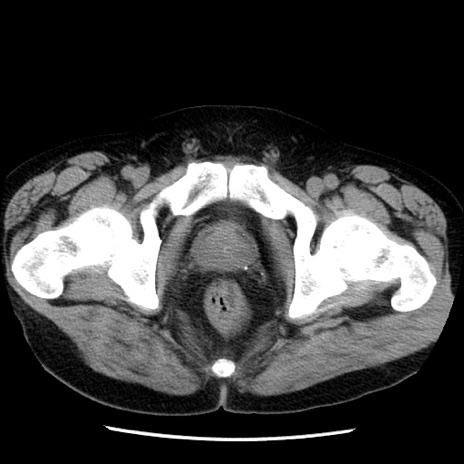

症例29(横断像)

【症例】40歳代男性

【現病歴】2日前から胃痛あり。徐々に周期的な激痛に変化した。本日になっても激痛があるため受診。

【身体所見】意識清明、BT 38-39℃台あり、腹部:膨満、やや硬、右下腹部に圧痛あり。

【データ】WBC 8500、CRP 23.26